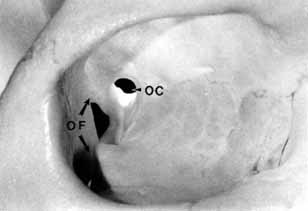

The orbital apex has two major openings, the orbital fissure and the optic canal (Fig. 1). The orbital fissure is divided into a superior and inferior portion by the tendon of Zinn, the inferior insertion for the tendinous anulus of Zinn (Fig. 2).1,4 (The anulus of Zinn is completed by the origins of the rectus muscles and the superior tendon of Lockwood.) Structures emanating through the optic canal (the optic nerve, ophthalmic artery, and orbital sympathetic nerves) as well as some structures coursing through the superior orbital fissure (the superior and inferior branches of the oculomotor nerve (cranial nerve III), the abducens nerve (cranial nerve VI) and the nasociliary branch of the ophthalmic division (cranial nerve V1) of the trigeminal nerve pass through the anulus of Zinn.

Fig. 1 Two openings are present at the orbital apex: the orbital fissure (OF) and the optic canal (OC).